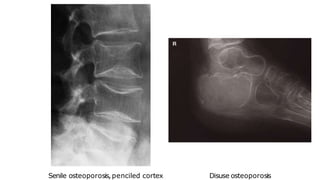

Osteoporosis

🠶Osteoporosis isthe consequence of a deficiency of

protein

🠶Osteoporosis predisposes to fractures

🠶The changes of osteoporosis are best seen in the spine

🠶Causes:

idiopathic, often subdivided according to age of onset, e.g.

juvenile, postmenopausal, senile.

Cushing’s disease and steroid therapy

disuse.

Disuse osteoporosis

Senile osteoporosis,penciled cortex